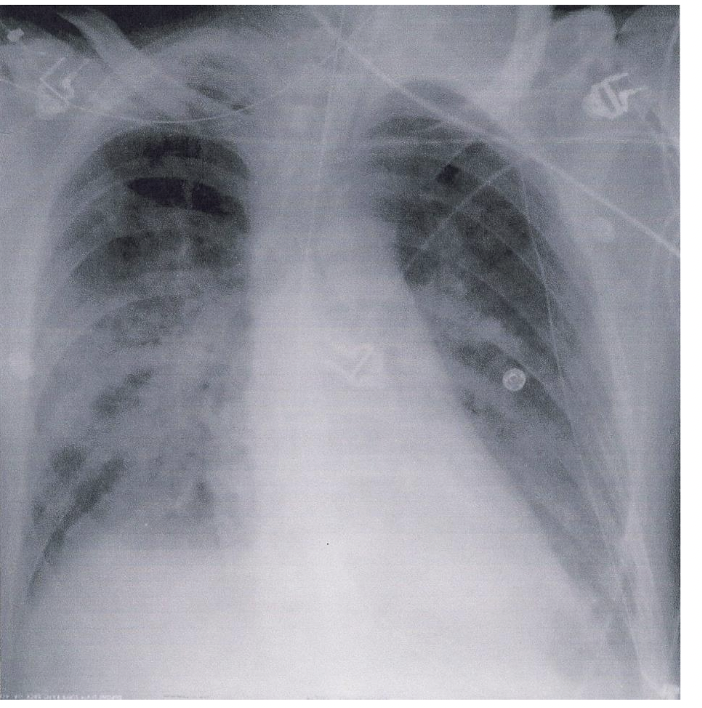

• Kliniske tegn: akutt lungeskade, latensperiode, langsomt innsettende respiratorisk dysfunksjon med takypne og takykardi, økt respiratorisk arbeid og forteninger på rtg thorax (diffuse interstielle, oftest bilaterale). PCWP < 16 mmHg